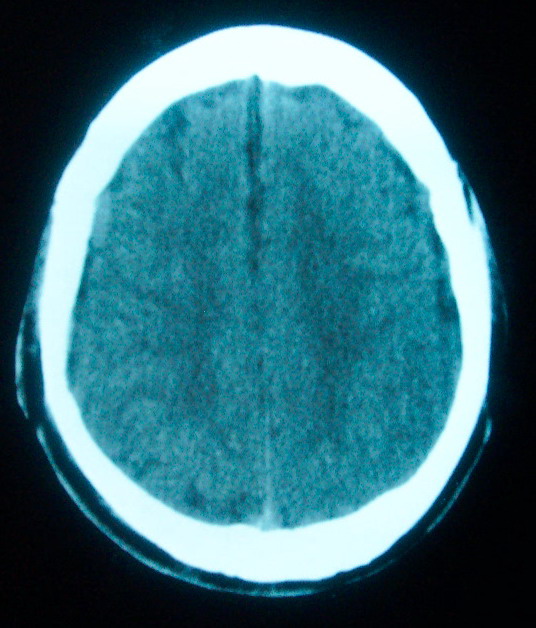

m     29    外伤1天   ct发现左额脑沟异常   请分析

我认为仅仅是左侧额叶脑回局部发育不良,脑沟与蛛网膜下腔略扩大而已没有巨脑回、硬膜下积液等情况。